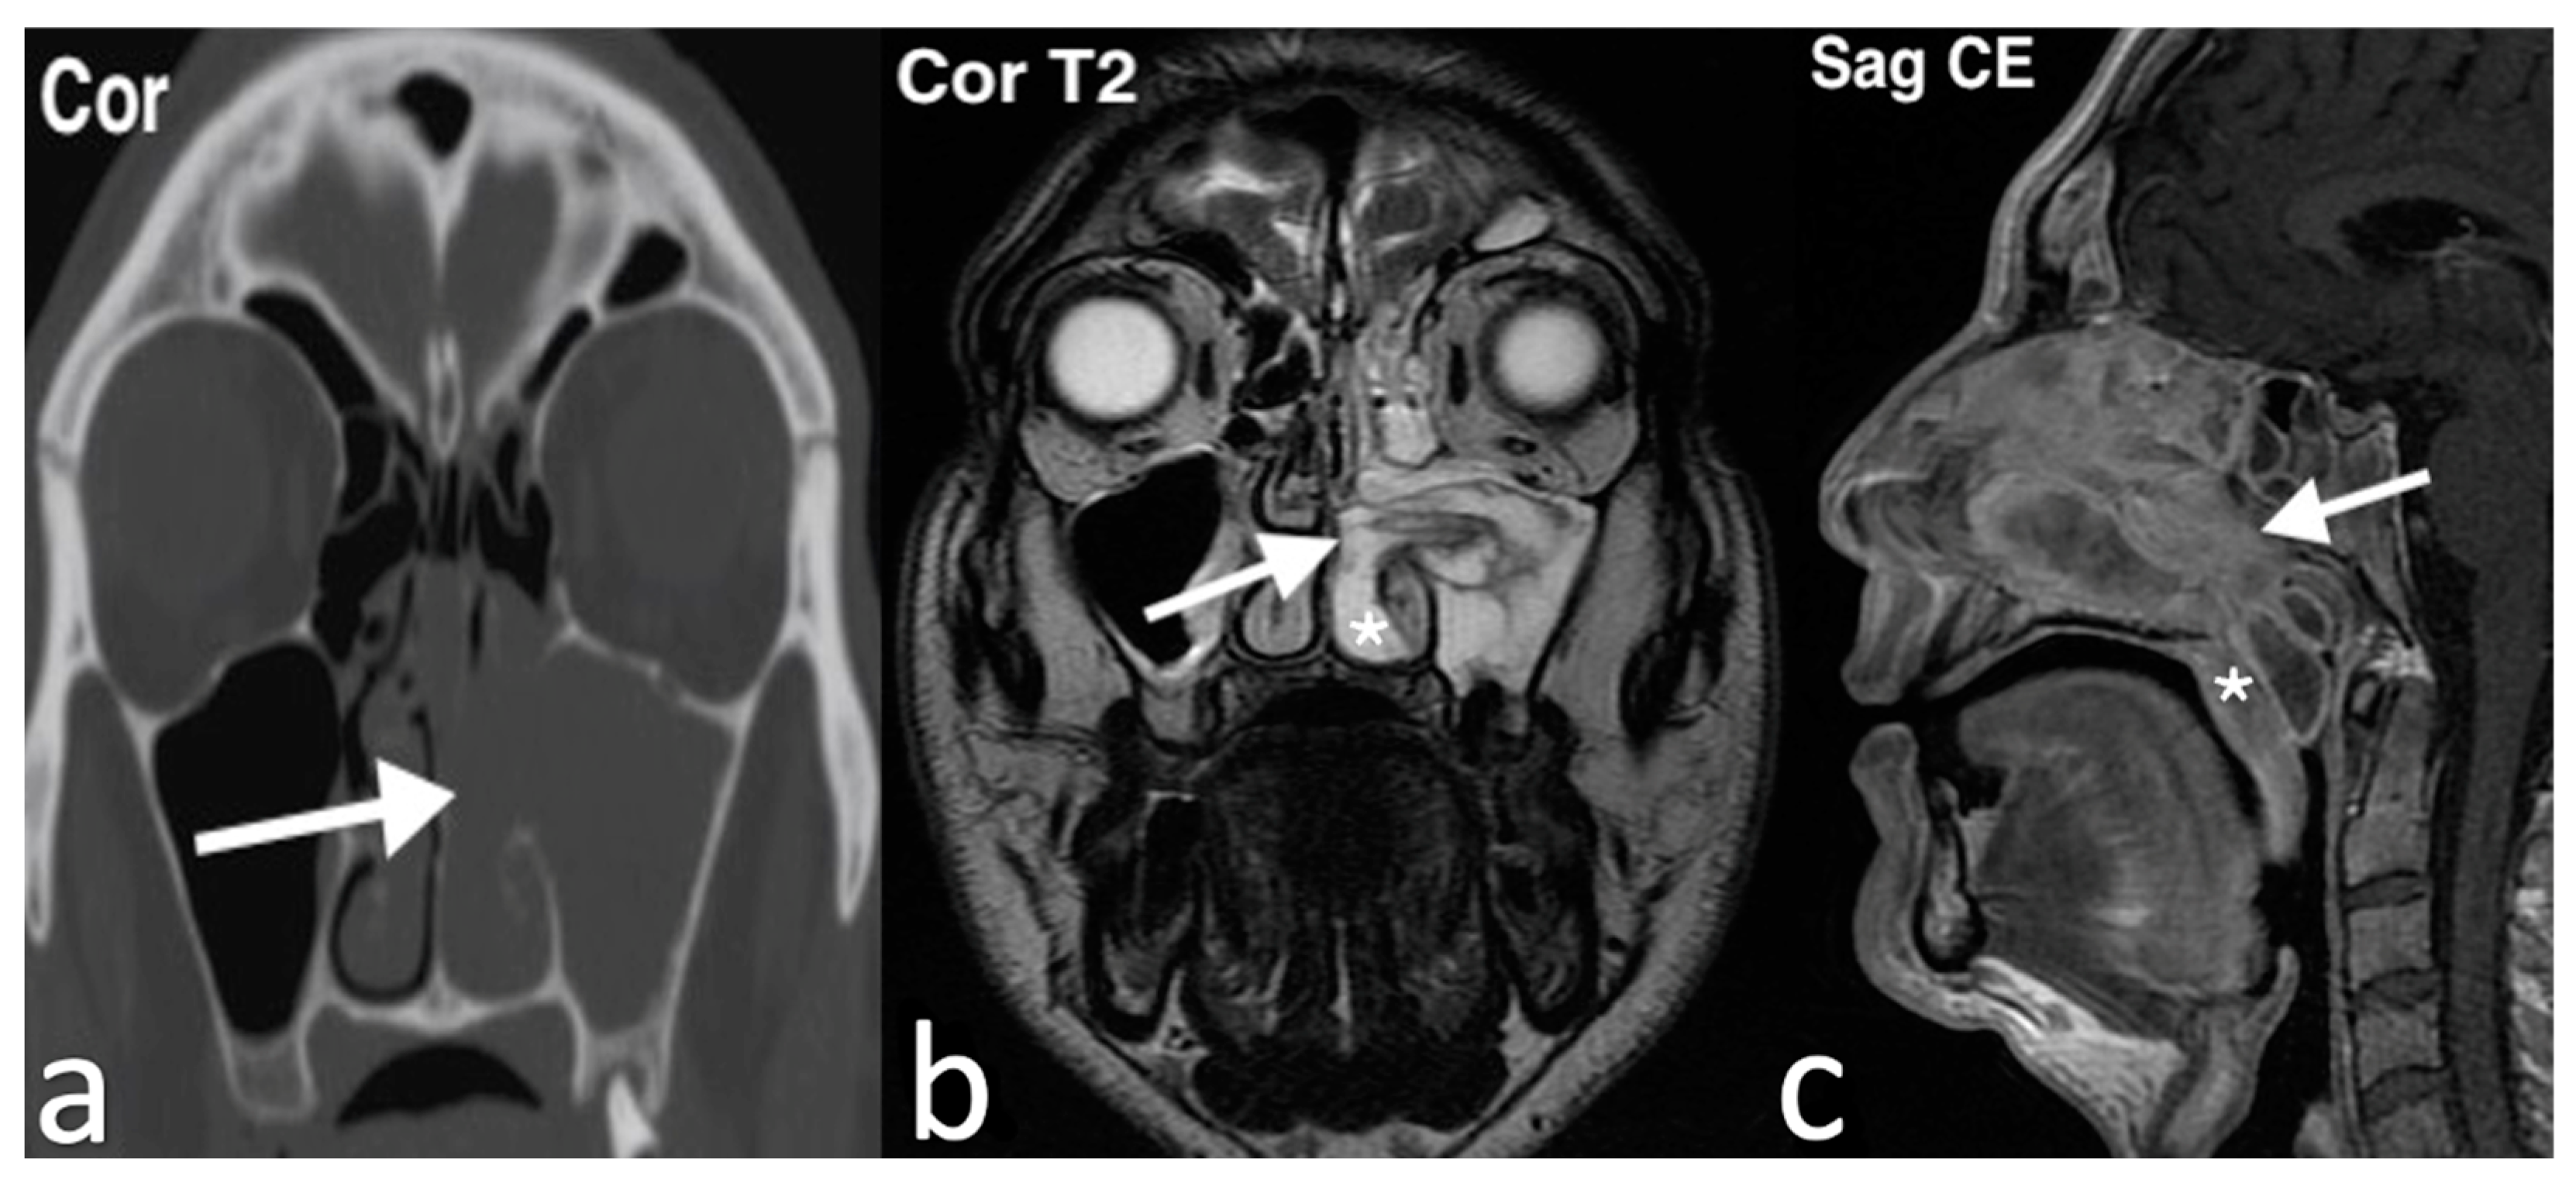

3.2.8. Antrochoanal Polyp

3.2.9. Lipoma

3.2.10. Sinonasal Tract Angiofibroma